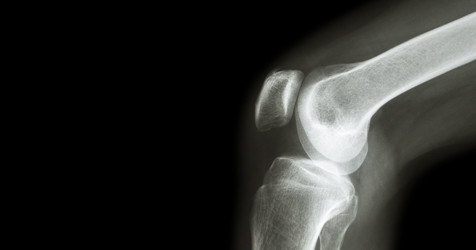

We believe in a careful examination which will begin with the evaluation of the patient's medical history and records. Later a thorough physical examination may take place. Radiological studies such as X-rays, CT scans, and MRIs for a deep musculoskeletal physical examination. Factors such as age, medical history, results of other examinations and diagnosis are taken into account when making suggestions for the treatment of the patient

The doctors at the KIMS Joint Replacement Surgery Hospital in Hyderabad are experienced in a variety of hip and knee joint replacement techniques. Joint arthroplasty, also known as total joint reconstruction, is a common surgical procedure in KIMS, it includes a total knee replacement or a single-compartment knee replacement for the knee. However, only a limited number of patients are suitable candidates for an osteotomy. i.e. a bone realignment treatment.

i. Hip and Knee Replacement: KIMS aim to not only become the top hip and knee replacement hospital in Hyderabad but be recognised all across the world. In hip replacement surgery acetabulum, i.e. the hip socket or the demus is replaced. Similarly, in knee replacement surgery the damaged cartilage, gliding surface or ligament is replaced or reconstructed.